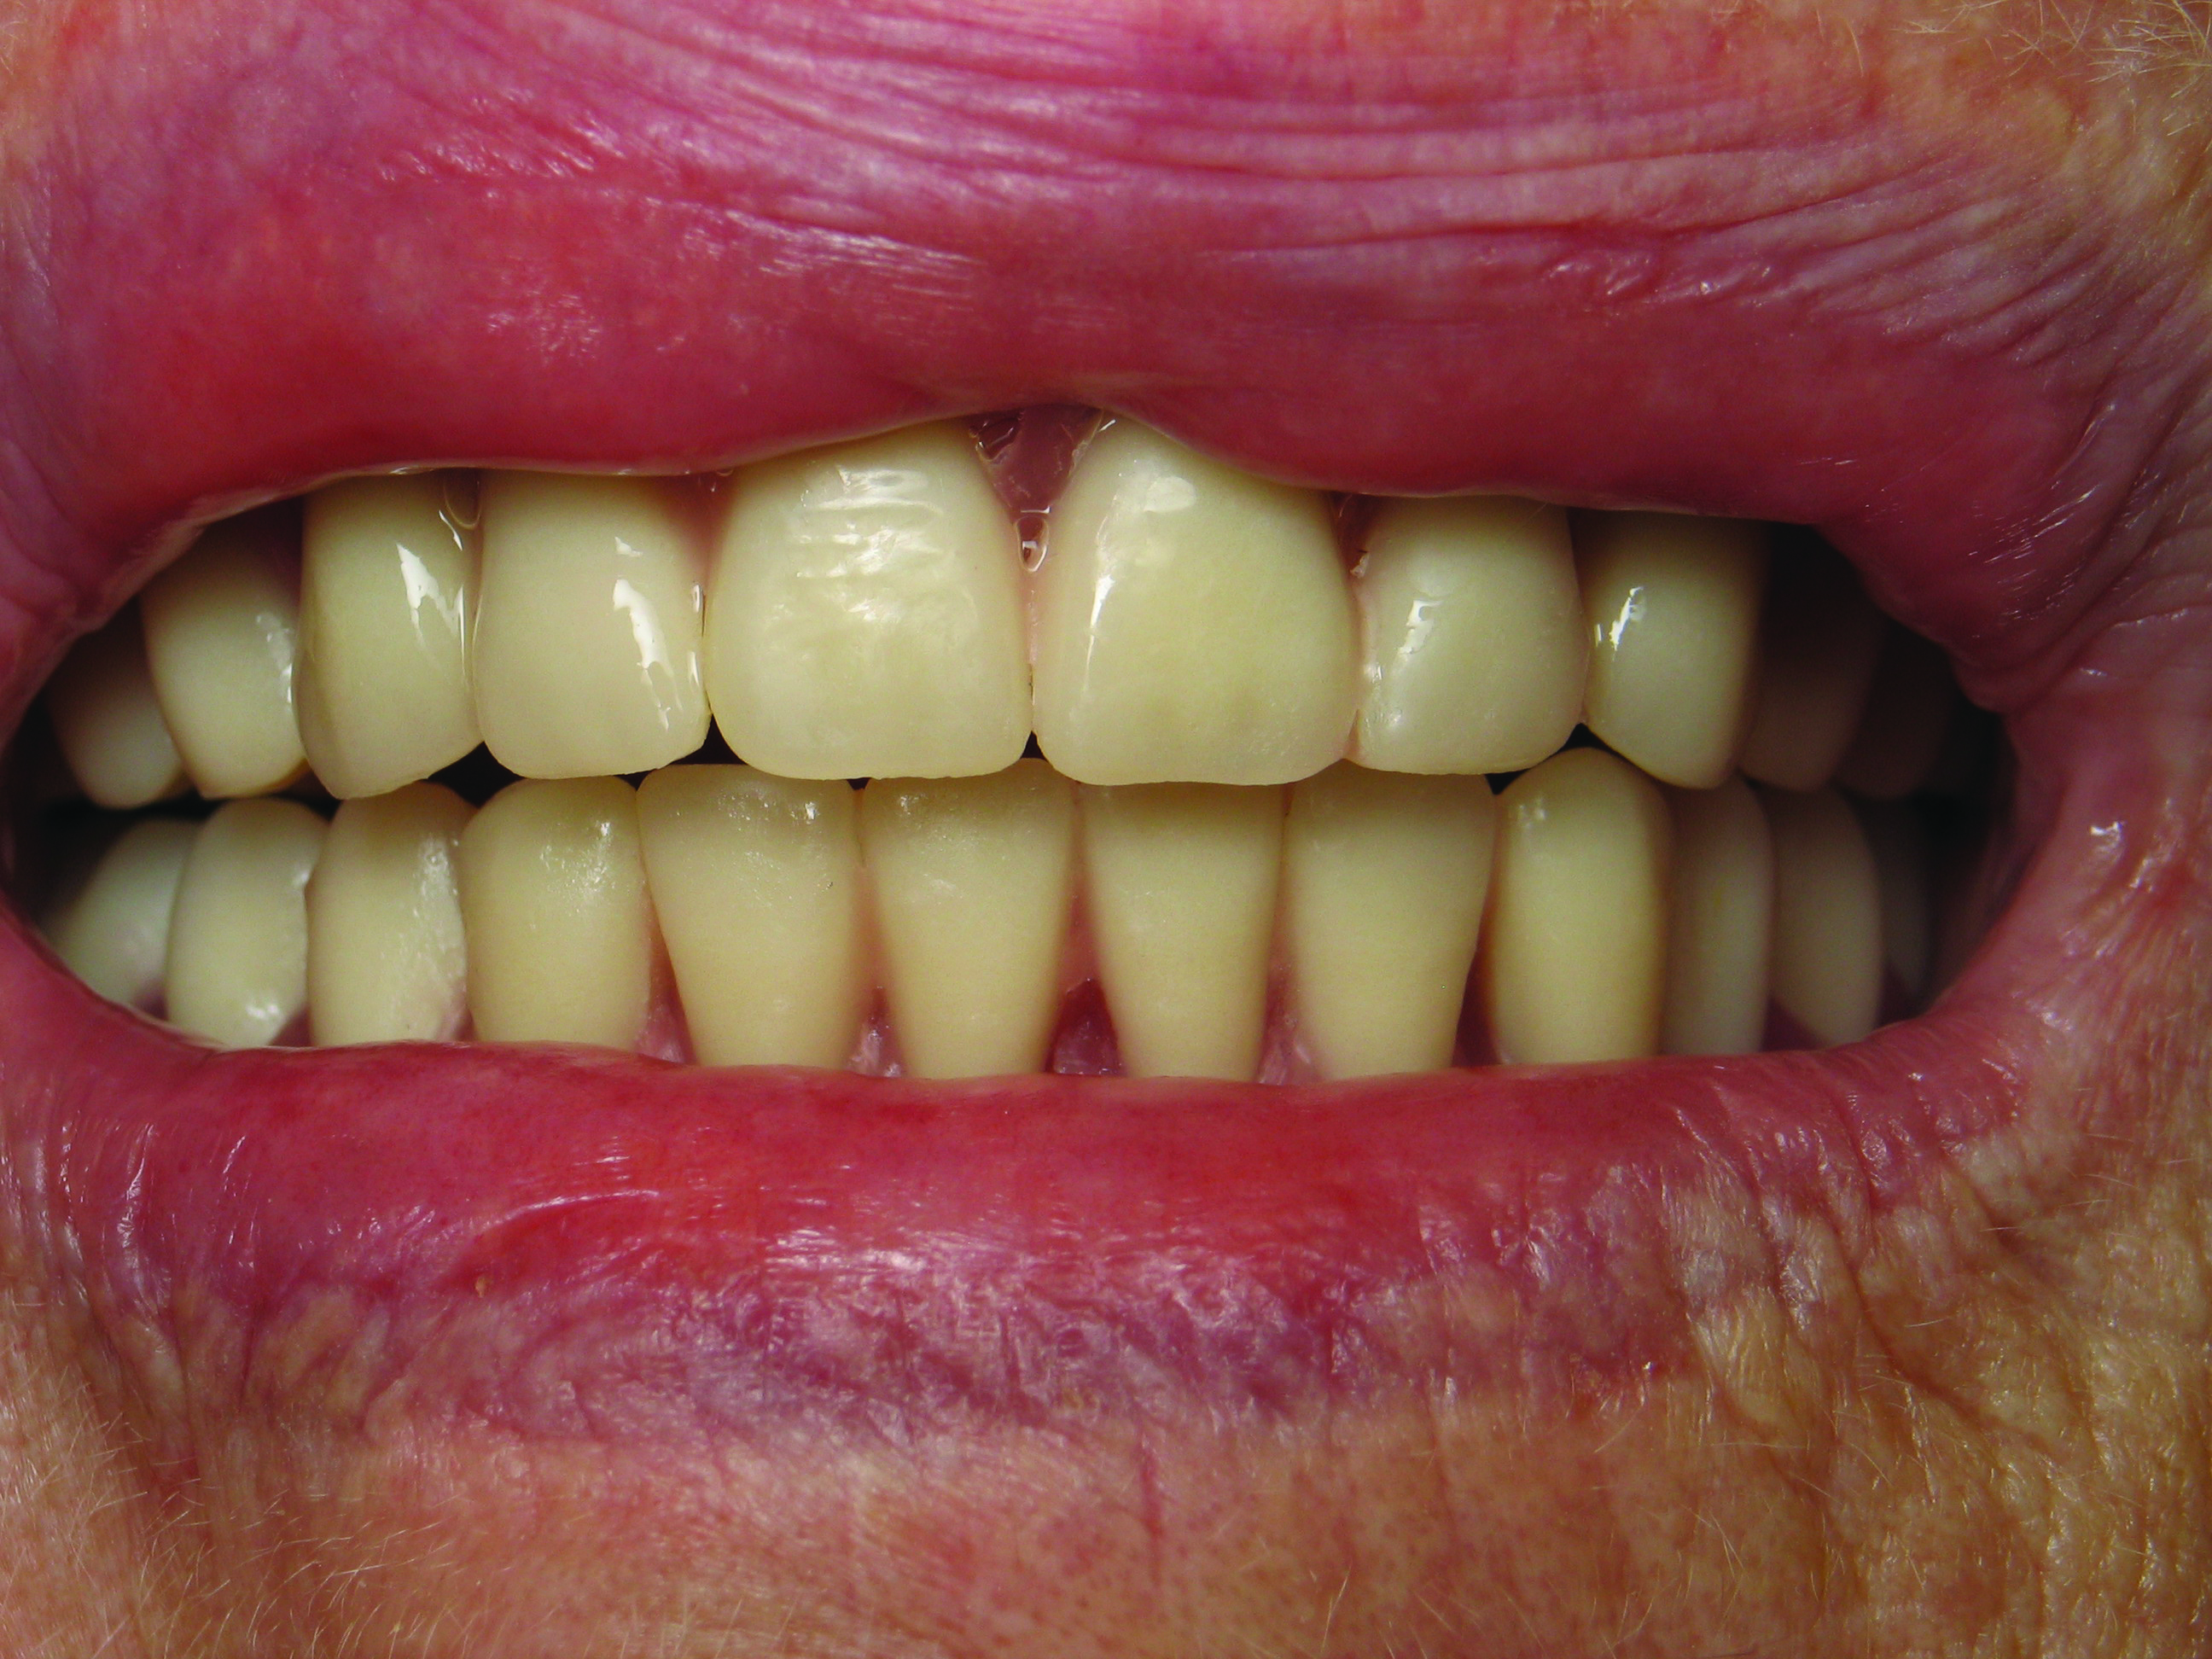

For the next appointment, the dentist receives a denture set-up to try in. Here is the final chance to make any substantial changes to the denture. The dentist verifies the fit, esthetics, vertical dimension, and phonetics (Figure 4 and Figure 5) to ensure that the patient can speak, verify the tooth shape, and select the shade. Because the set-up is normally in wax, there is wide latitude to make changes in position, fit, and feel for the patient. Once both patient and dentist are satisfied, the set-up is returned to the laboratory for final processing. On the laboratory side, after processing, the dentures should be checked again to ensure no changes happened during the process and are returned to the dentist ready for insertion.3,4

Fig 4. Set-up try-in verifying fit, borders, bite, and tooth position.

Figure 4

Fig 5. Set-up try-in to verify esthetics and phonetics and make adjustments as needed to tooth position.

Figure 5